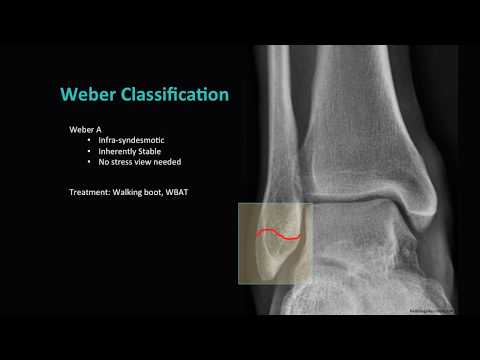

Distal Fibula Fractures

My Ankle Sprain Diagnosis - FRACTURED FIBULA (Weber type A)